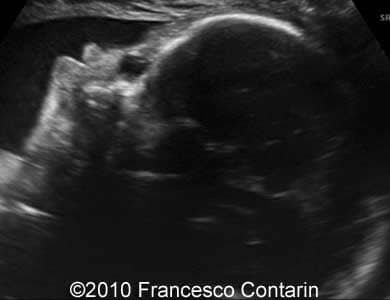

Image 3

: Image shows sagittal view of the dacryocystocele.